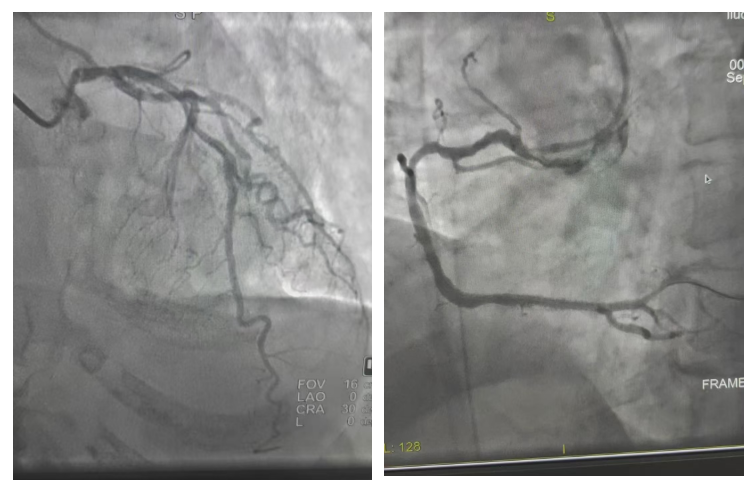

•核心作用:可呈现冠状动脉情况,如左冠状动脉(含左主干、回旋支、左前降支、对角支、钝缘支等分支)、右冠状动脉(含窦房结支、动脉圆锥支、锐缘支、左室后支、后降支等分支)的状况,还能通过介入治疗前后对比(如回旋支近段重度狭窄术前与支架植入后血管通畅的对比),判断血管病变及治疗效果。